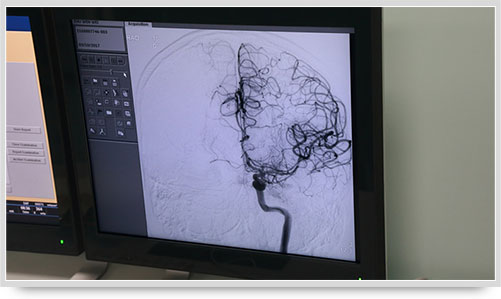

同时,手术台前的液晶显示仪屏幕上清晰地现显出导管的路径,在李主任的操作下准确到达指定检查部位,各条血管的“庐山真面目”清晰可见。

在铅玻璃橱窗另一侧的介入手术室内,身穿铅衣的李振并主任娴熟地进行一系列的操作:局麻、穿刺、置入导管鞘、上导管......在X线透视下,顺利开始全脑血管造影术。

弓上造影、超选到颈内动脉、椎动脉......在数字减影技术下,注入显影剂后,导管经患者右侧股动脉在体内推进,由于股动脉离脑血管距离较远,中间“路程复杂”,对施术医生的要求非常之高。